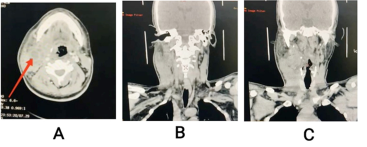

Diabetes mellitus is a common disease in developing countries and the complications are feared by many physicians and surgeons. One such rare and dangerous complication is parapharygeal abscess which can spread via its intricate anatomical site to other deep neck spaces. We present the case of a young male who is a known uncontrolled diabetic presented to us with neck swelling and toxic symptoms and managed successfully with timely surgical intervention by exploring all neck planes to evacuate purulent material thus speeding up the recovery process.

Parapharyngeal space; Diabetes Mellitus; Klebsiella; Abscess; DNSI.Parapharyngeal spaceDiabetes MellitusKlebsiellaAbscessDNSI